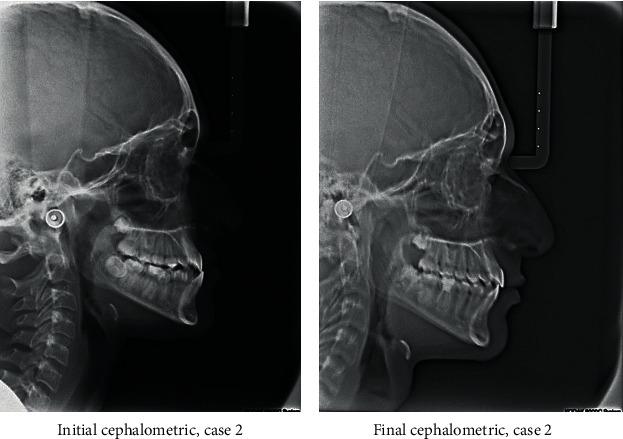

Distalization is a conservative method that is utilized in orthodontics to gain space by moving posterior teeth distally. It may be combined with other space gaining strategies, such as expansion, or can be used alone. Many methods have been used for distalization. These methods differ significantly in their place, whether to be extraoral or intraoral, site of action in upper and/or lower arch, and cooperation needed by the patient if it is removable or fixed. This review illustrates some of the most commonly used methods for distalization with a brief presentation of three cases that incorporated successful distalization techniques.